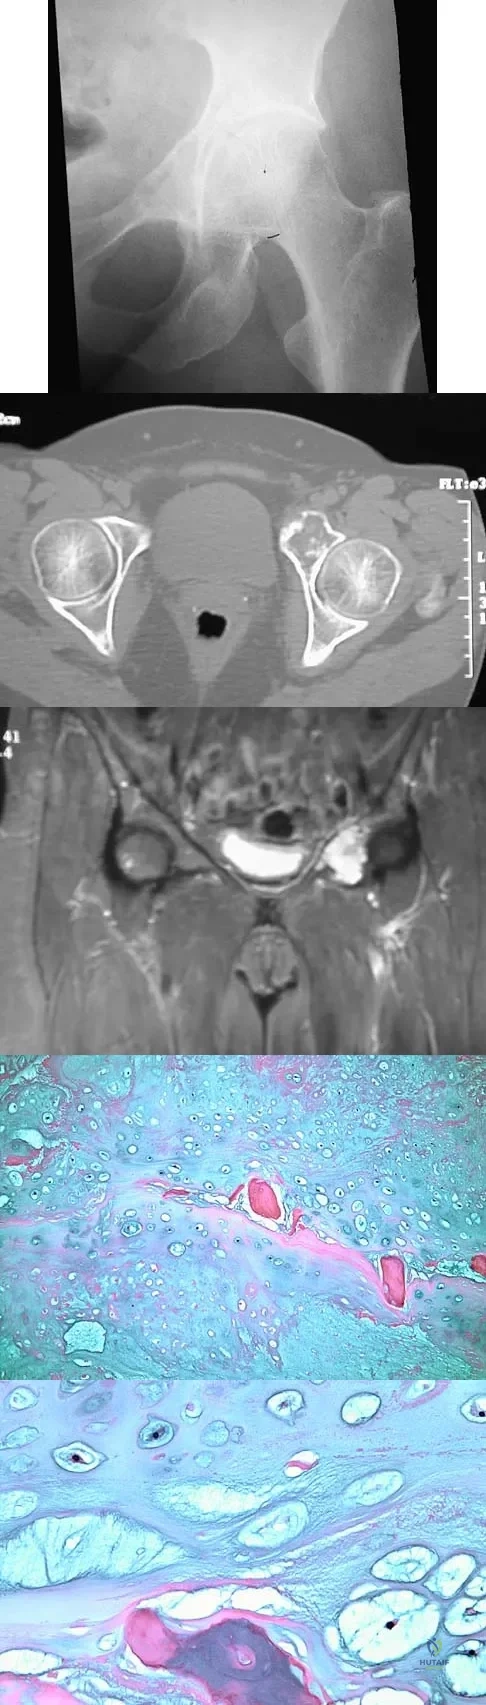

A 43-year-old woman has had pain in the left hip for the past 2 months. A radiograph, CT scan, MRI scan, and biopsy specimens are shown in Figures 16a through 16e. What is the most likely diagnosis?

Explanation